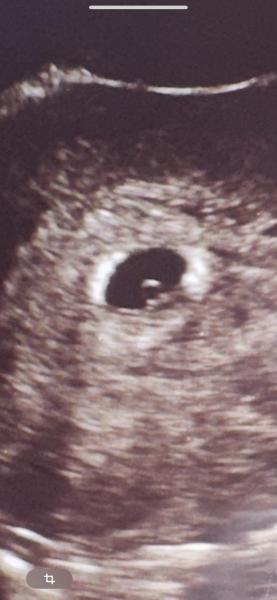

Hey ihr Lieben, ich habe mich in die Ramzi-Methode eingelesen und die wichtigsten Infos (inkl. Zeichnungen etc.) zusammengetragen. Jetzt hänge ich aber an meinem eigenen vaginalen Ultraschallbild fest und komme einfach nicht weiter 🥲 Vielleicht kennt sich hier ja jemand gut damit aus und kann mir helfen: Wo befindet sich bei meinem Bild die Plazenta? Soweit ich gelesen habe, bedeutet rechts = Junge und links = Mädchen (zumindest in den ersten Wochen). Ich hänge euch mal mein Bild an – würde mich sehr über eure Einschätzung freuen! Das Bild ist schon richtig gedreht, oben die kleine Kurve, unten die große :)